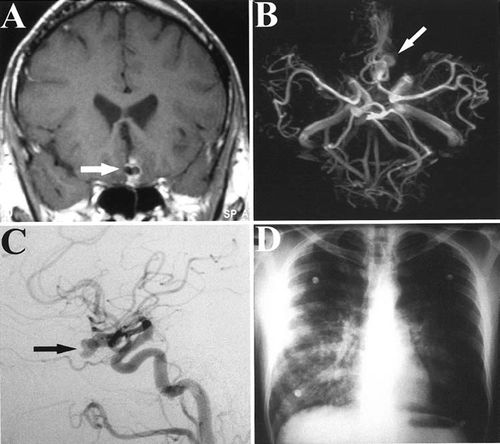

当我初诊时认为这应该是个血管夹层,但出乎意料是个颅内血管的动脉瘤,上网搜索确实类似的病例很少,仅有一例类似情况:

47岁男性,因氧气耗竭急速升上水面,他昏迷40分钟后苏醒,但出现剧烈头痛,在当地按照气压伤治疗。2天后他回国入住当地医院,医生做CT发现是蛛网膜下腔出血,遂行DSA,发现大脑前交通动脉上有一8X14mm的动脉瘤(图5),其发病机理并不清楚。(ReichardtKA, NabaviA, Barth H, et al. Barotrauma as apossible cause of aneurysmal subarachnoid hemorrhage. Case report. Journalof Neurosurgery. 2003,98 (1): 180-182)。

图5. A、B和C分别是MRI的T1相、MRA和DSA,都提示大脑前交通动脉上的动脉瘤